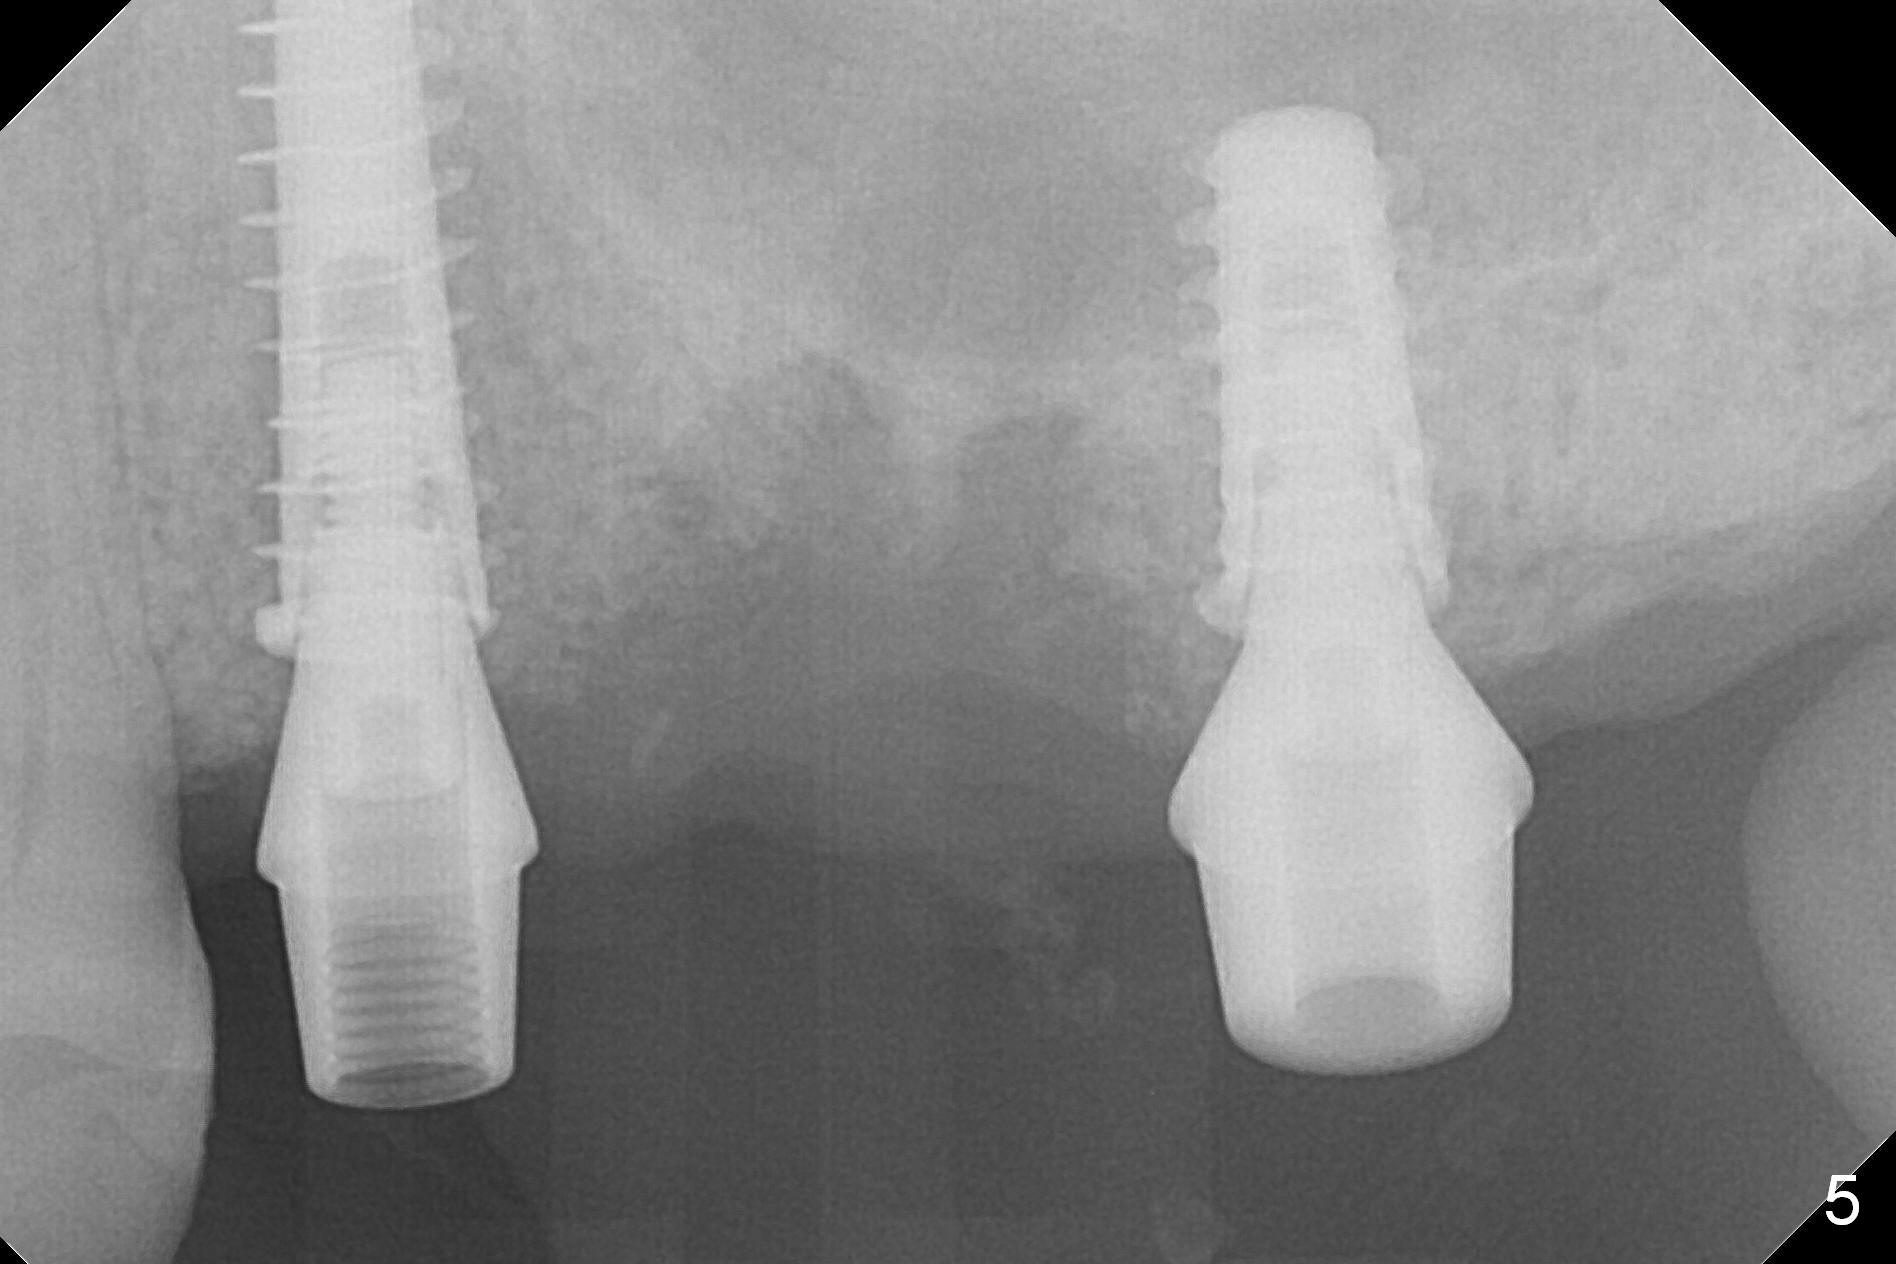

To prevent sinus membrane perforation, a piece of PRF membrane is inserted into the osteotomy, followed by mixture of autogenous bone, allograft (.5-1.5 mm) and Osteogen for sinus lift. A 5x9 mm implant is placed with 50 Ncm as well as 6.5x4(3) mm abutment (Fig.5).